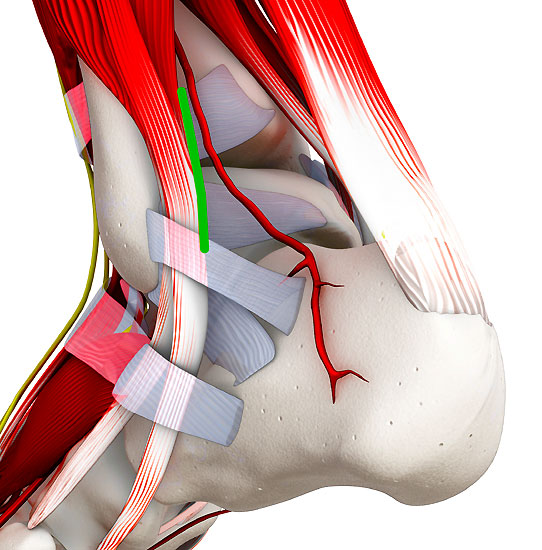

Abbildung 2: K-Draht Spreizer. Dieser erlaubt eine Distraktion des Gelenks über 1,8 mm Kirschnerdrähte. Diese Technik hilft in nahezu allen Fällen eine Innenknöchelosteotomie zu vermeiden.

Abbildung 2

• Spreizer mit Bohrungen für Kirschnerdrähte (Abbildung 2).

Je nach Lage des Knorpeldefektes sind verschiedene Zugänge möglich. Ziel ist einen guten Zugang zum Defekt zu erreichen bei gleichzeitiger Vermeidung einer Innenknöchelosteotomie.